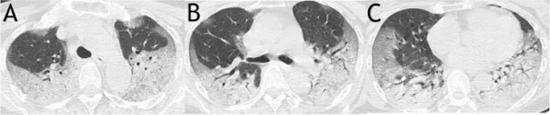

Studies Use SIRD Model to Forecast COVID-19 Spread; Examine Patient CT Scans to Correlate Clinical Features With MortalityTwo studies of the coronavirus COVID-19 outbreak recently published in the open-access journal PLOS ONE. The first study, published March 31, 2020, was conducted by Constantinos Siettos from the Universita degli Studi di Napoli Federico II, Italy, and colleagues. The authors used a Susceptible-Infected-Recovered-Dead (SIRD) model calibrated with the reported data between January 11 and February 10, 2020, and forecasted the evolution of the outbreak in the epicenter of the outbreak, Hubei, China up until February 29. With these parameters, they forecasted that at least 45,000 would be infected and 2,700 would die by February 29—in fact, in Hubei, around 67,000 are known to have become infected, while the death toll was around 2800 in this time period. The authors also used the SIRD model to estimate COVID-19’s R0 value, an estimate of contagiousness which reflects the average number of people who may catch an infection from one contagious person. Across various scenarios, their estimate of R0 based on the available data was around 2.5. Assuming a high degree of underreporting of mild cases of COVID-19 in their data, they estimated a mortality rate in the total population of around 0.15% for the virus. Furthermore, based on a scenario assuming an order of 20-fold scaling of the number of infected in the total population, their study predicted a decline of the outbreak at the end of February in Hubei. Indeed, during the last days the number of new infected cases has dropped significantly. Siettos notes: “This is the first study based on a mathematical modelling approach that has provided relatively accurate three- week-ahead forecasts. Importantly, to the best of our knowledge this is the first study based on a mathematical modelling approach suggesting that the actual number of the infections in the total population is of the order of twenty times more than those reported, and that the mortality rate in the total population is about ~0.15% ie, significantly less than reported 2% to 3%.Our findings imply that for the case of Hubei (with a 60m population), around 2% to 3% of the total population in Hubei has been actually infected by coronavirus.” The second study, published March 19, 2020, was conducted by Mingli Yuan and colleagues from the Central Hospital of Wuhan, Hubei province, China. The researchers studied 27 patients infected with COVID-19 and admitted to the Central Hospital of Wuhan. In this patient group, the authors associated clinical features identified from CT scans of patients’ lungs with eventual outcomes. They scored patients based on features they observed such as ground glass opacity, abnormality on both sides, and widespread distribution of pathology in the lungs, to produce an overall severity score for each patient. Of the 27 patients, who were mostly older adults (median age 60), 17 (63%) recovered and were discharged from hospital, while 10 (37%) died of the virus. Patients with underlying health conditions including hypertension, diabetes, and cardiac disease were more likely to die of the virus than patients without such comorbidities, and older patients were also more likely to die, though there was no difference between genders. Patients with a higher (more severe) score at CT scan were much more likely to die of COVID-19 – the average score of patients who died was 30, compared with 12 in patients who recovered. Yuan adds: “This study allows us to compare radiologic findings with the mortality of patients infected with COVID-19.”

Image Credit: Yuan et al, 2020 (CC BY 4.0) Source: PLOS |